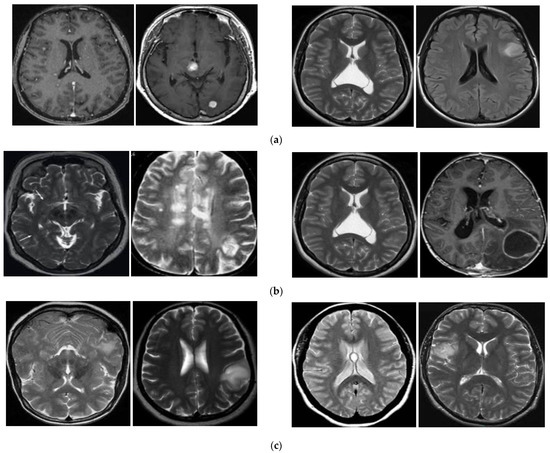

We performed a five-fold cross-validation procedure to evaluate the performance of our proposed method using the BT-Small dataset. For this purpose, we randomly divided the entire BT-Small dataset into five equal parts and assigned them to the training, validation, and testing sets. However, in contrast to the conventional five-fold cross-validation procedure that uses most of the data for training and less data for testing, we used data from one part for training and validation and data from the remaining four parts for the testing dataset, as our study focuses on a small training dataset for the brain tumor image classification system. Among the images in one part that were assigned as the training and validation sets, we randomly selected an equal small number of images in each class for training, and the other images were used for validation. Based on this division, we used the training set to train the classifiers, which were then validated using the validation set. As the FS network mentioned in Section 3.6 requires a support set to evaluate the similarity function between a test image and the images in the support set, we randomly selected a subset of the testing set to form a support set for the FS network. The remaining data of the testing set were assigned to the final test set, which was used to measure the performance of the classifiers on real-world data. The experiments were repeated five times by iterating the training, validation, support and testing set division. Finally, the overall performance of the classification system was measured by taking the average performance of all five experiments. Table 4 summarizes the characteristics of the BT-Small dataset with detailed information on the training, validation, and testing sets. As can be observed from this table, the test dataset is much larger than the training and validation sets. In Figure 7, we show some examples of brain images from the BT-Small dataset.

As explained in Section 3.1, the BT-Large dataset contains brain images that belong to three predefined categories: Meningioma, glioma, and pituitary, as shown through some examples in Figure 8. This dataset is different from the BT-Small dataset, which contains images of two categories of tumor (with tumor region) and non-tumor (without any tumor region) images. As the BT-Small dataset contains images with and without tumors, the difference between the images in the two categories in the BT-Small dataset is high. Therefore, we can easily distinguish between tumor and non-tumor images. However, the difference between images among categories in the BT-Large dataset was low because all images in the BT-Large dataset contained tumors. In addition, the BT-Small dataset contained two image classes (categories), whereas the BT-Large dataset contained three image classes (meningioma, glioma, and pituitary). Therefore, classifying images into a large number of predefined categories using a small amount of training data is also a more difficult problem than classifying images into a small number of predefined categories. Therefore, the classification performance of the BT-Small dataset was much better than that of the BT-Large dataset, as shown in Table 7, Table 8, Table 9 and Table 10. For a 3-class classification system, a random guessing system produces an accuracy of about 33.333% that is much lower than our classification accuracy (55.792% mentioned in Table 10). In addition, Table 13 shows that our proposed method also outperformed various classification methods when using small data for training. From this result, we think that our algorithm successfully enhanced the classification performance compared to previous classification methods. From our experimental results, we showed that the lack of training data lead to reduction in performance of conventional classification systems. Knowing this problem, our proposed method can be used in real-world applications when there is less data for training the classification system such as a new or less common disease is presented.